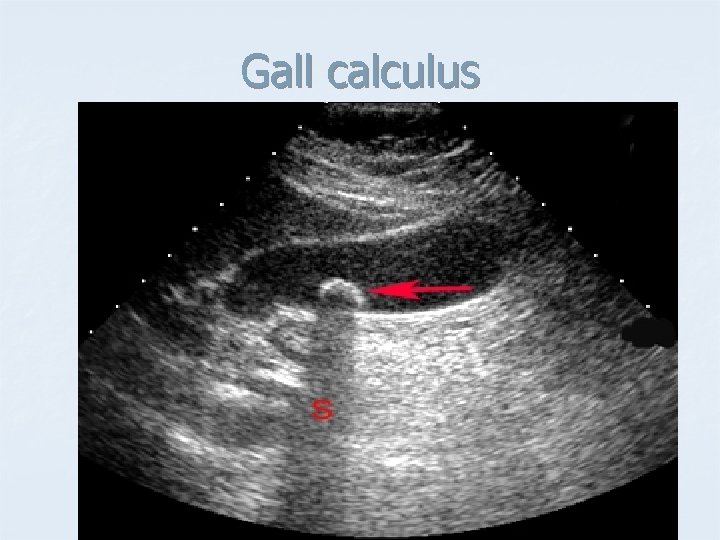

Gall calculus